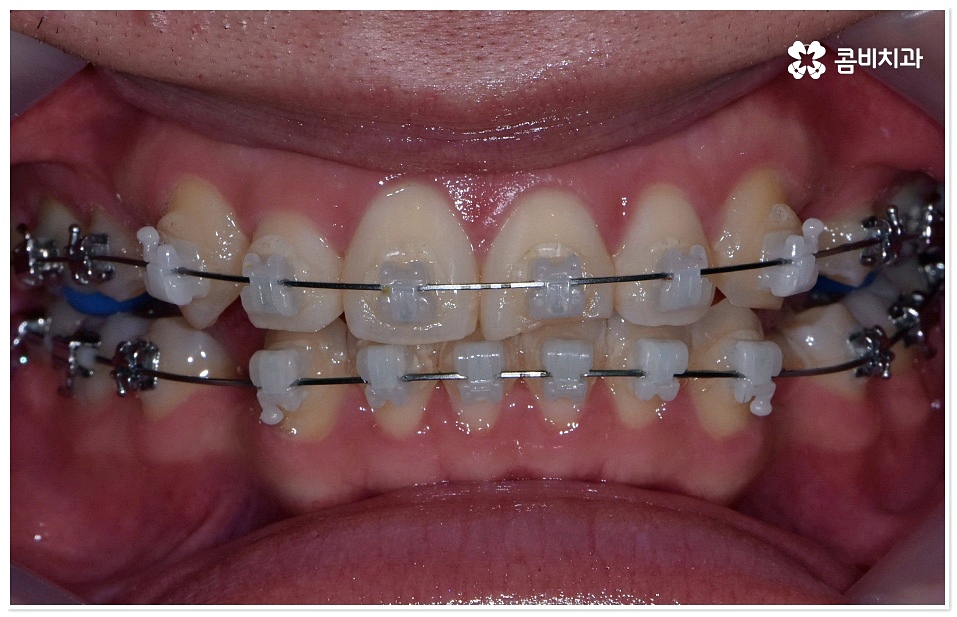

하지만 막상 덧니치아교정 을 받고 싶어도 실제로 시작하기까지 여러 가지 망설여지는 포인트가 있으실 거예요. 그 중에서도 겉으로 드러나는 장치 때문에 부담을 느끼시는 분들이 있을 수 있는데 최근에는 관련 의료 기술이 발전하면서 교정 장치가 눈에 덜 띄도록 하는 방법과 장치들이 나와 환자분들이 느끼시는 심미적인 부담을 줄여주고 있으니 먼저 검진 및 상담부터 받아보시길 권유드리고 있어요. 특히 교정치료 기간 동안 스스로 탈착이 가능한 투명교정 등 환자의 상태에 맞춘 다양한 방법을 알아볼 수 있으니 숙련된 의사선생님과 충분히 상담한 후 자신에게 적합한 계획을 세우실 필요가 있어요.

또한 통상적으로 1년 반에서 2년 반 정도 걸리는 비교적 긴 기간 동안 치료를 받아야 하는 상황에 대해서 고민하시는 분들도 있을 수 있는데 이 역시도 환자분들마다 상황이 다 다르기 때문에 먼저 정확한 검진부터 받아보시면 좋을 거예요.

교정 치료란 특수한 장치를 이용해 치아를 원하는 방향으로 이동시켜 치아 배열과 교합을 올바르게 개선해 주는 과정으로 각자의 구강 구조가 다 다르기 때문에 정밀 검사를 통해 환자분들 각각의 치아 모양과 각도, 위치, 교합 뿐 아니라 잇몸 건강 상태 및 상악과 하악의 관계와 같은 구강 내 상황과 함께 입술, 전체 안모 등 대칭과 균형의 측면에서 모든 부분을 다각적이고 입체적으로 분석한 후 세밀한 맞춤 계획을 수립하는 것이 중요할 수 있는데요.